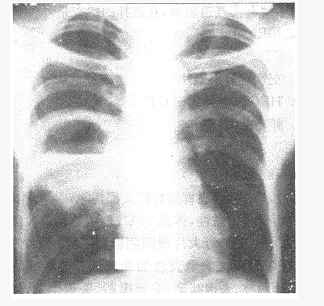

阅读胸片

病灶部位()